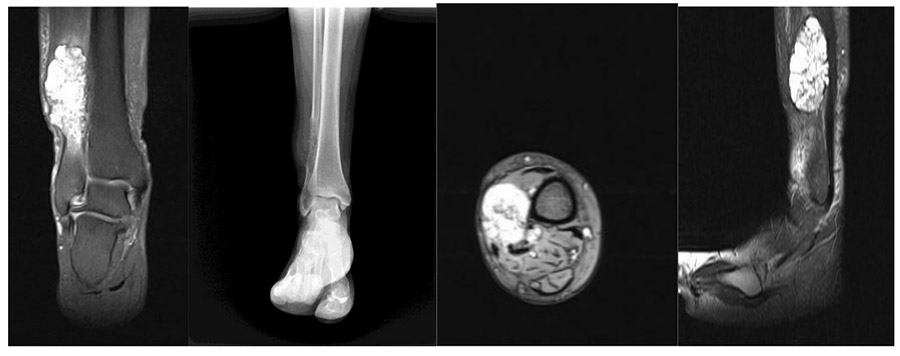

CASE 55: Lung cancer metastasis to the right fibula

Before the surgery: X-ray shows a lytic lesion in the distal femur, and MRI shows a large soft tissue component.